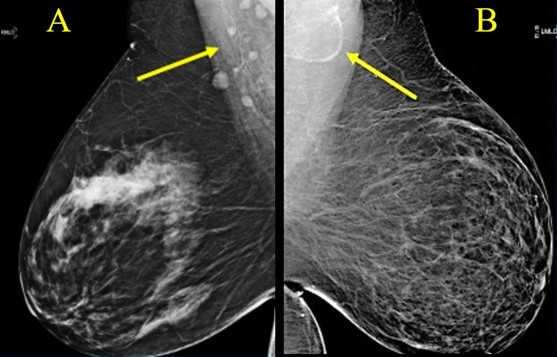

Once an emerging tool, rectal MRI is now the gold standard for staging, enabling assessment of the T stage and detecting key prognostic features such as mesorectal fascia involvement (MRF) and extramural venous invasion (EMVI) (Fig. 1).

Fig. 1—59-year-old patient with rectal cancer with extramesorectal

vessel involvement, consistent with T category of T4b. Axial (top) and

axial oblique (bottom) T2-weighted images show rectal tumor that extends

through extramesorectal vein (arrow), which according to expert opinion

warrants classification as T4b.

Dr. James Costello (ARRS) will lead a session on foundational principles of T staging, MRF, and EMVI, emphasizing actionable strategies to refine reports and guide multidisciplinary teams. Building upon Dr. Costello’s foundation, Dr. Verity Wood (RANZCR) addresses the myriad nuances of assessing lymph nodes and how to identify poor prognostic tumor deposits. Pointing out pitfalls left and right, her lecture during the 2026 ARRS Annual Meeting Global Exchange with RANZCR will provide the latest imaging criteria to help radiologists render more confident interpretations.